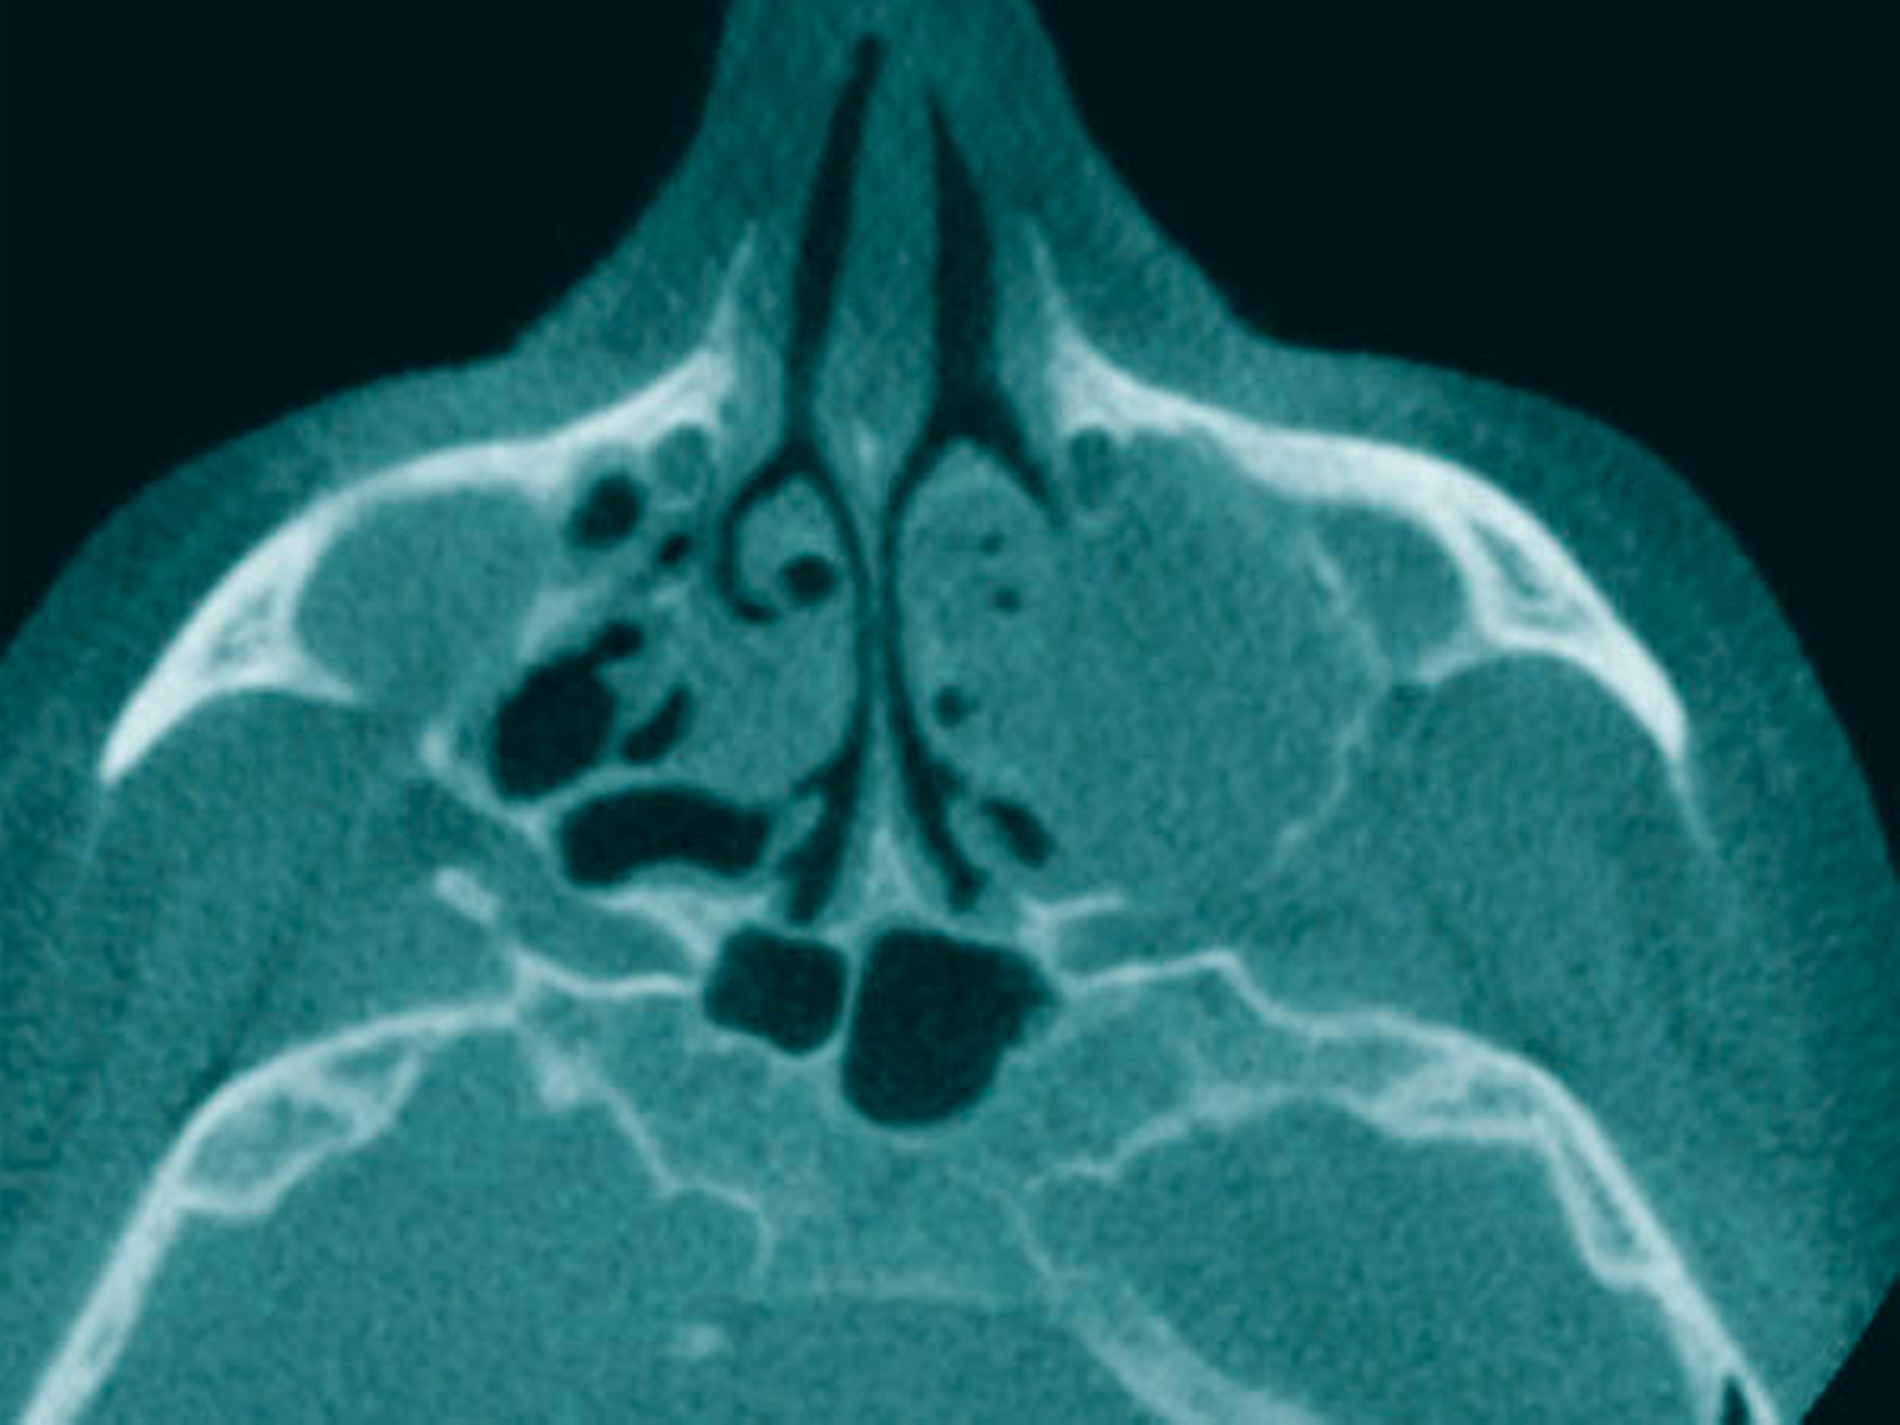

Als sich die Patientin an der Universitätsmedizin vorstellte, erfolgte primär die Anfertigung einer Computertomografie (CT) des Kopfes mit Kontrastmittel, in der sich eine vollständige Verschattung der linken Kieferhöhle sowie eine apikale Transluszenz an Zahn 26 darstellte (Abbildung 1).

Die Allgemein- und Familienanamnese der Patientin war bis auf eine medikamentös eingestellte Hypothyreose unauffällig. Extraoral bestand kein auffälliger Befund, insbesondere keine Druckdolenz oder Nervdefizit über der Kieferhöhle links. In Regio 27 zeigte sich eine Mund-Antrum-Verbindung nach frustranem Deckungsversuch, aus der sich seröse Flüssigkeit entleerte (Abbildung 2). Der Zahn 26 reagierte negativ auf Perkussion und war avital. Nach sorgfältiger Aufklärung erfolgte die Resektion des Befunds in Intubationsnarkose. Folgend auf die Extraktion des Zahnes 26 (Abbildung 3) wurde eine Kastenresektion der linken Maxilla von distal des Zahnes 25 bis in den Tuberbereich bei makroskopischem Einhalten eines Sicherheitsabstands von 0,5 cm durchgeführt. Das narbig anmutende Gewebe in der Kieferhöhle wurde ausgeschält und en bloc mit dem Oberkieferresektat entfernt (Abbildung 4). Der Knochen wurde hier belassen, da er klinisch und radiologisch nicht infiltriert war.